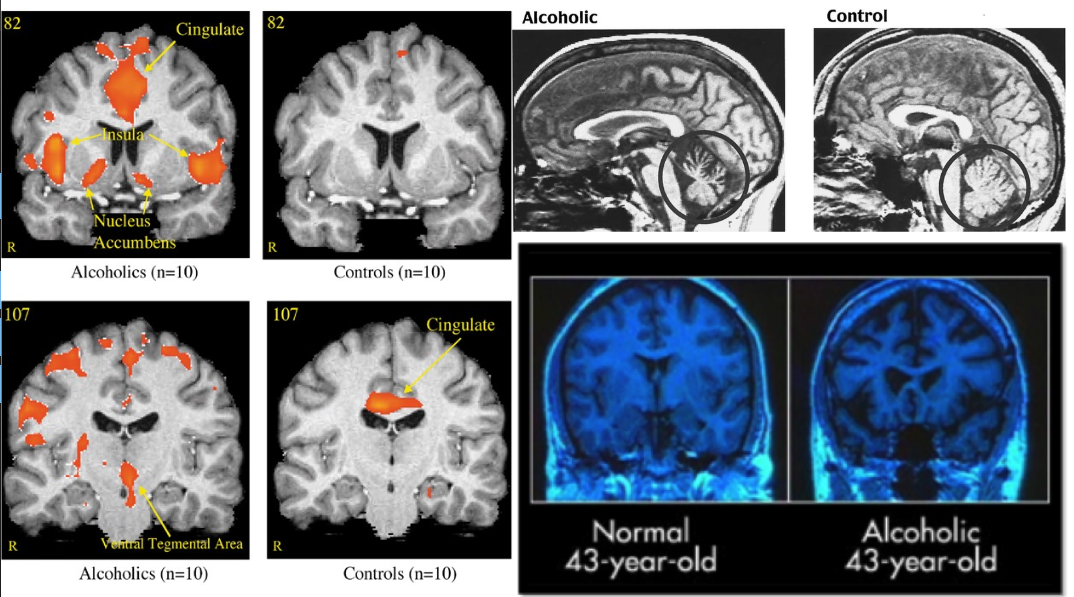

알콜을 많이 마시면 신경퇴행이 일어난다.

(신경퇴행이라고해서 류마티즘이 떠오르는 사람도 있겠지만, 신경퇴행성질환은 훨씬 더 무서운 것들을 떠올려야 한다 - 알콜성 치매, 파킨슨 병, 알츠파이머 병 등이 있다. )

정확한 부위는 Neocortex/신피질이다.

뇌의 외측 레이어에 있고 기억과 관련된 부분이며 우리가 생각하고 계획하고 원초적인 충동(Primitive Drive)을 조절하는 능력을 담당한다. 매일 두 세잔 씩 마시는 건 논란의 여지 없이 몸(뇌)에 좋지 않다.

그렇다면 ‘적당한 음주’ 혹은 ‘소량의 음주’가 장기적으로 미치는 영향은 어떨까?

2022년 3월 영국에서 낸 논문이 드디어 이 질문에 대답을 한다.

알콜 섭취와 뇌 구조에 대한 관계를 36,678명의 30대 이상의 건강한 중년층이 참여한 이미징 데이터를 통해 분석한 결과이다.

알콜섭취는 전반적인 뇌 수축의 효과가 있고 하루에 한 두잔 역시 부정적인 영향을 미친다는 것을 보여준다.

신피질이 얇아지는 것이 확인되었다. 즉 신피질과 뇌 다른 부위의 신경세포들이 감소한다는 것이다.

하루에 한 두 잔을 마시건, 주말에 14잔을 마시건, 한 주에 7~14잔을 마시건 뇌를 살펴보면 뇌의 신경퇴행이 발생하고 있다는 이야기이다.

참고자료: https://www.nature.com/articles/s41467-022-28735-5